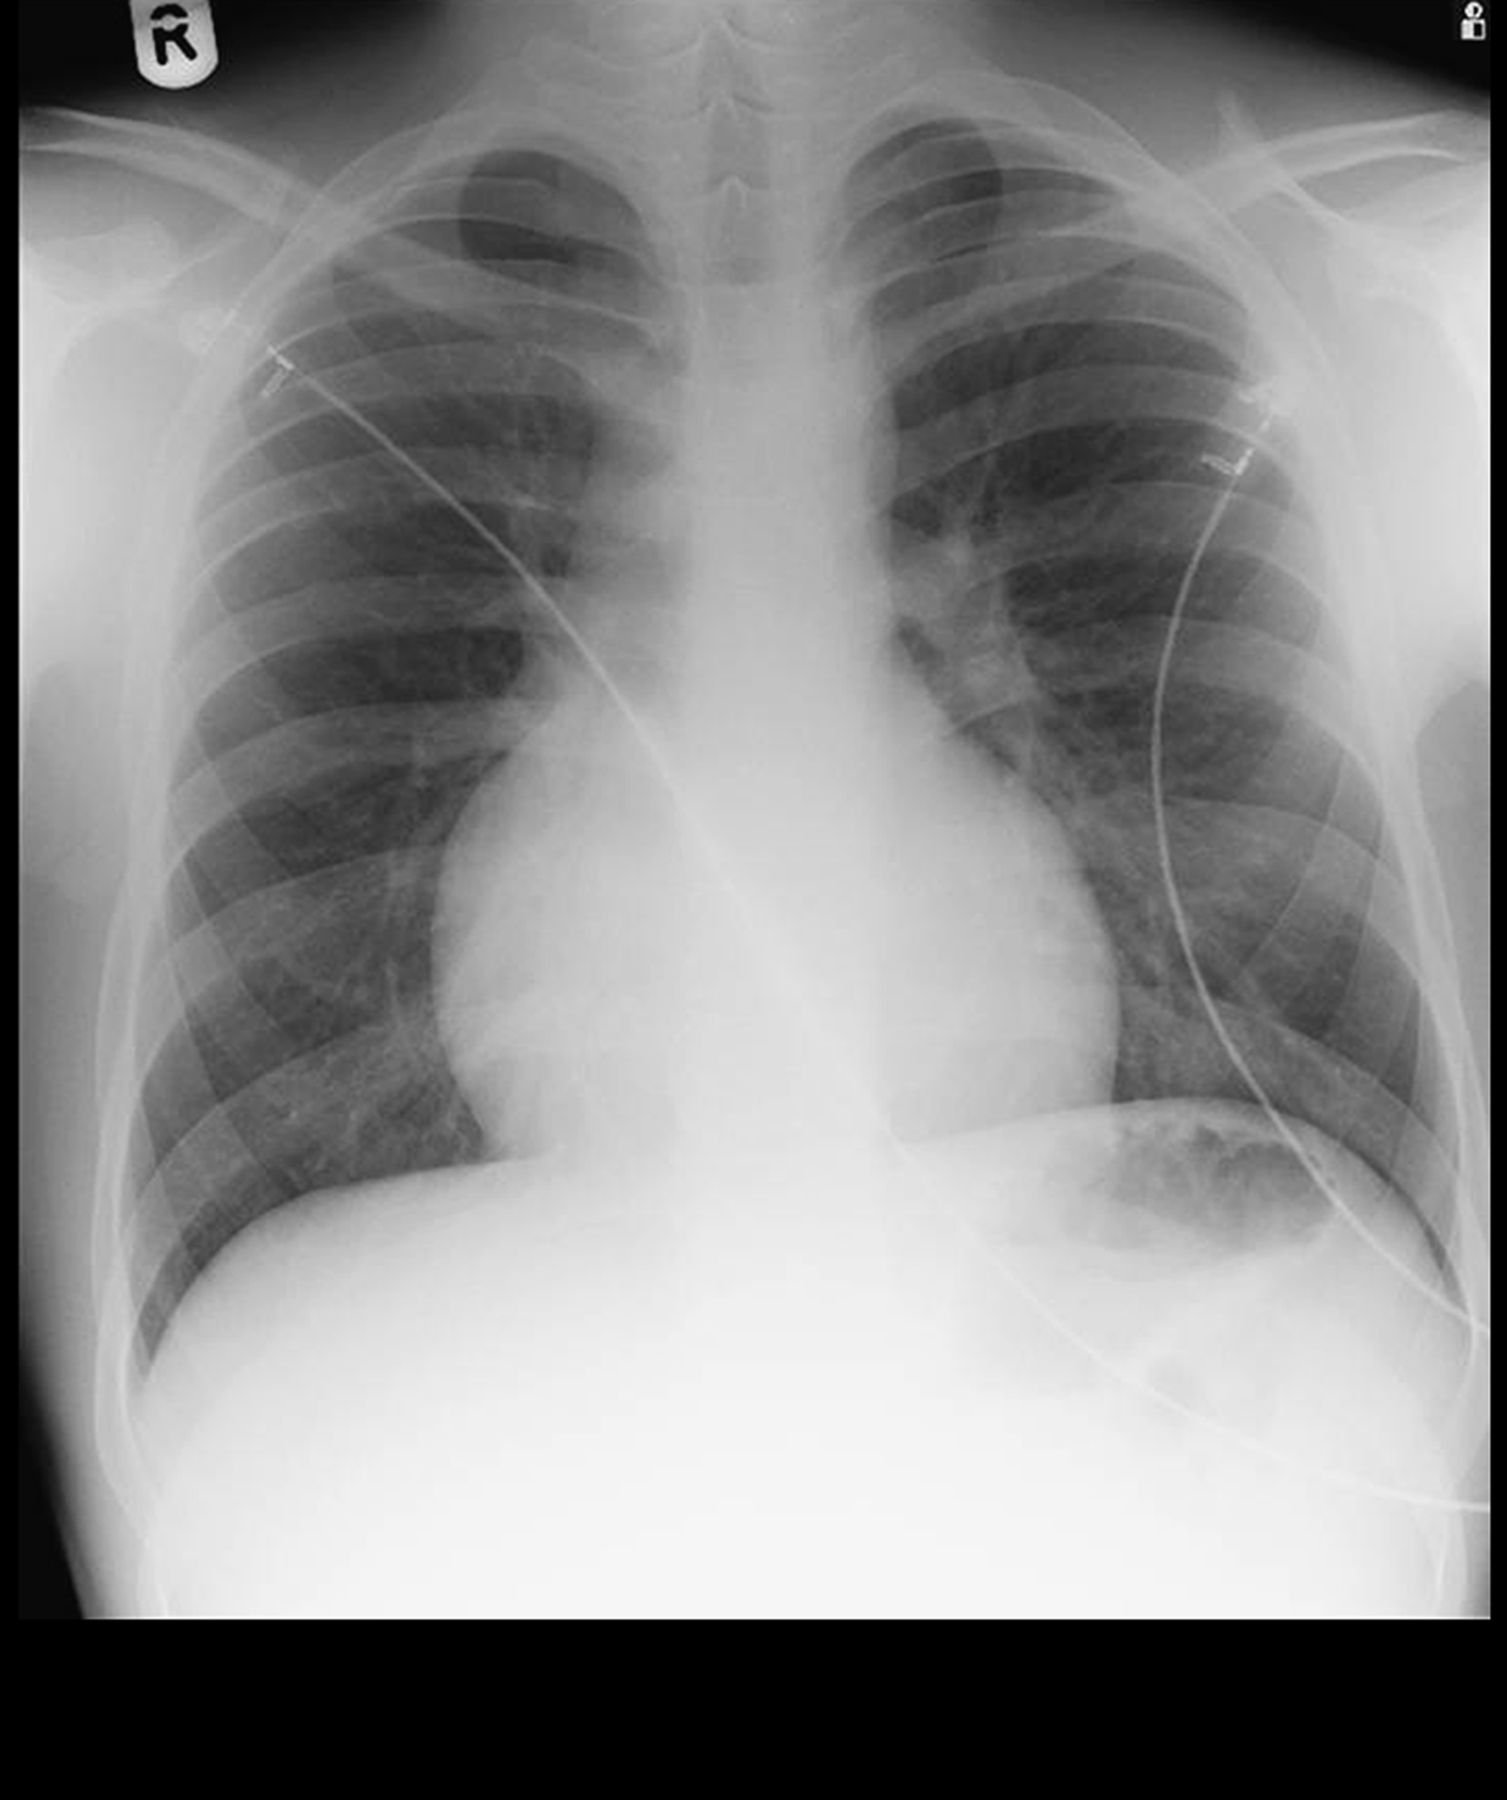

Chest X-ray. This test uses invisible electromagnetic energy beams to make images of internal tissues, bones, and organs onto film.